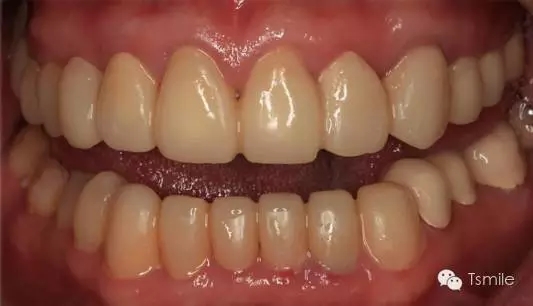

圖6:最終修復(fù)體完成

前兩個美學(xué)分析和美學(xué)表達(dá)過程已經(jīng)確定了患者滿意的最終的美學(xué)修復(fù)設(shè)計,也就是已經(jīng)確定了最終修復(fù)體的形態(tài)、大小、排列、牙齦曲線等各種美學(xué)參數(shù),美學(xué)實現(xiàn)就是復(fù)制前面已經(jīng)確定的美學(xué)設(shè)計的過程,包括牙體預(yù)備、印模制取、修復(fù)體制作、修復(fù)體試戴粘接等過程。

例如面對一個牙列重度磨耗的美學(xué)修復(fù)患者,我們首先根據(jù)患者主訴和美學(xué)檢查形成美學(xué)設(shè)計,然后通過數(shù)碼圖像表達(dá)美學(xué)設(shè)計思想,制作診斷蠟型,口內(nèi)制作診斷飾面,更加真實地表達(dá)美學(xué)設(shè)計。根據(jù)患者的要求和口內(nèi)試戴情況調(diào)改診斷飾面,最終確定美學(xué)修復(fù)設(shè)計,即最終修復(fù)體的各種美學(xué)參數(shù)。接下來就是美學(xué)實現(xiàn)過程,在診斷飾面上進(jìn)行精確地牙體預(yù)備,制取印模和工作模型,技師按照最終診斷飾面的形態(tài)、大小和排列制作最終美學(xué)修復(fù)體,最后完成修復(fù)體粘接。